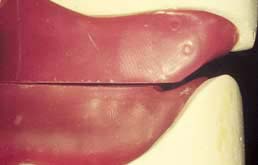

Dentists should be under no illusion that mucosally-supported partial dentures will, within a relatively short time, lose occlusal contact with the opposing arch as the underlying bone is resorbed; this type of denture cannot be relied upon to provide a lasting occlusion. In addition, the problem implied in the term ‘gum strippers’ is well known; a typical example is shown in Figure 3 illustrating the iatrogenic effects of selecting a mucosally- supported design. Simple relines are only likely toexacerbate the resorption.

| Fig 3 Gum stripper | Fig 4 Training denture |